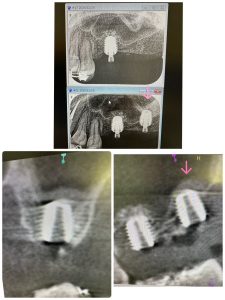

左上7番、デンサーリフト、20分で終わり

手前6番は5年前のインプラント

もう人工骨は使わないからね🤪

I.S.Q値はイマイチ😭